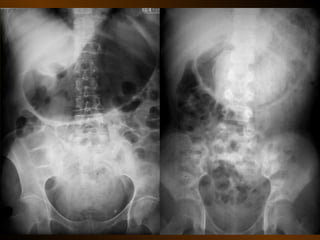

CĂNG GIÃN ỐNG TIÊU HÓA

• Căng giãn dạ dày

• Căng giãn tá tràng

• Căng giãn ruột non

• Căng giãn đại tràng

• Căng giãn ruột non lẫn đại tràng